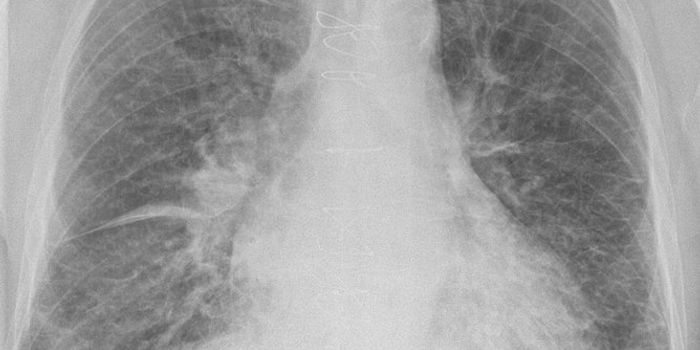

Cardiology is an ever-evolving branch of medicine concerned with disease and disorders of the heart. Cardiology trending provides articles and resources to keep you informed on risk factors, causes and prevention of heart disease, evidence-based research and advances in treatment.